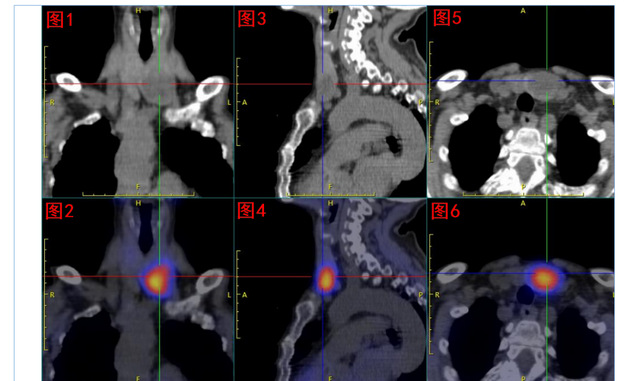

核医学科双时相甲状旁腺核素SPECT/CT显像发现:甲状腺左叶下极处显像剂异常浓聚,考虑为功能亢进甲状旁腺组织;但是该组织主体位于甲状腺左叶内,非甲状旁腺常见部位,遂反馈给吕荣主任医师团队,建议进一步行甲状旁腺及甲状腺超声检查。

99mTc-MIBI甲状旁腺SPECT/CT融合显像图:图1+2冠状位、图3+4矢状位、图5+6横断位,提示功能亢进甲状旁腺组织(十字线交叉处)。随后的超声提示:双侧甲状旁腺区多断面超声扫查未见明显异常占位性病变;双侧甲状腺结节,其中左侧叶内一枚33mm×19mm低回声、边缘光滑、内无强回声结节。颈部B超图:A、B(纵切面)分别显示甲状腺左叶、甲状腺右叶;左叶内一低回声结节。